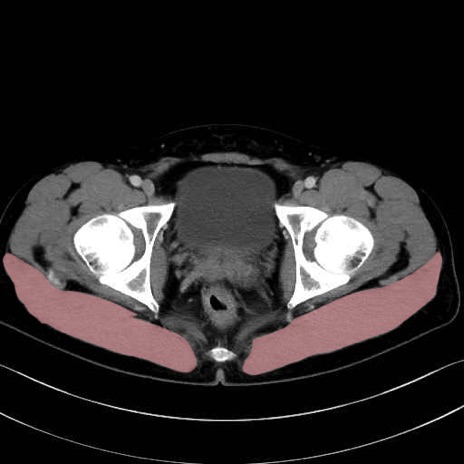

3. 殿部の筋肉(表層・中層・深層)

大殿筋 (Gluteus maximus)